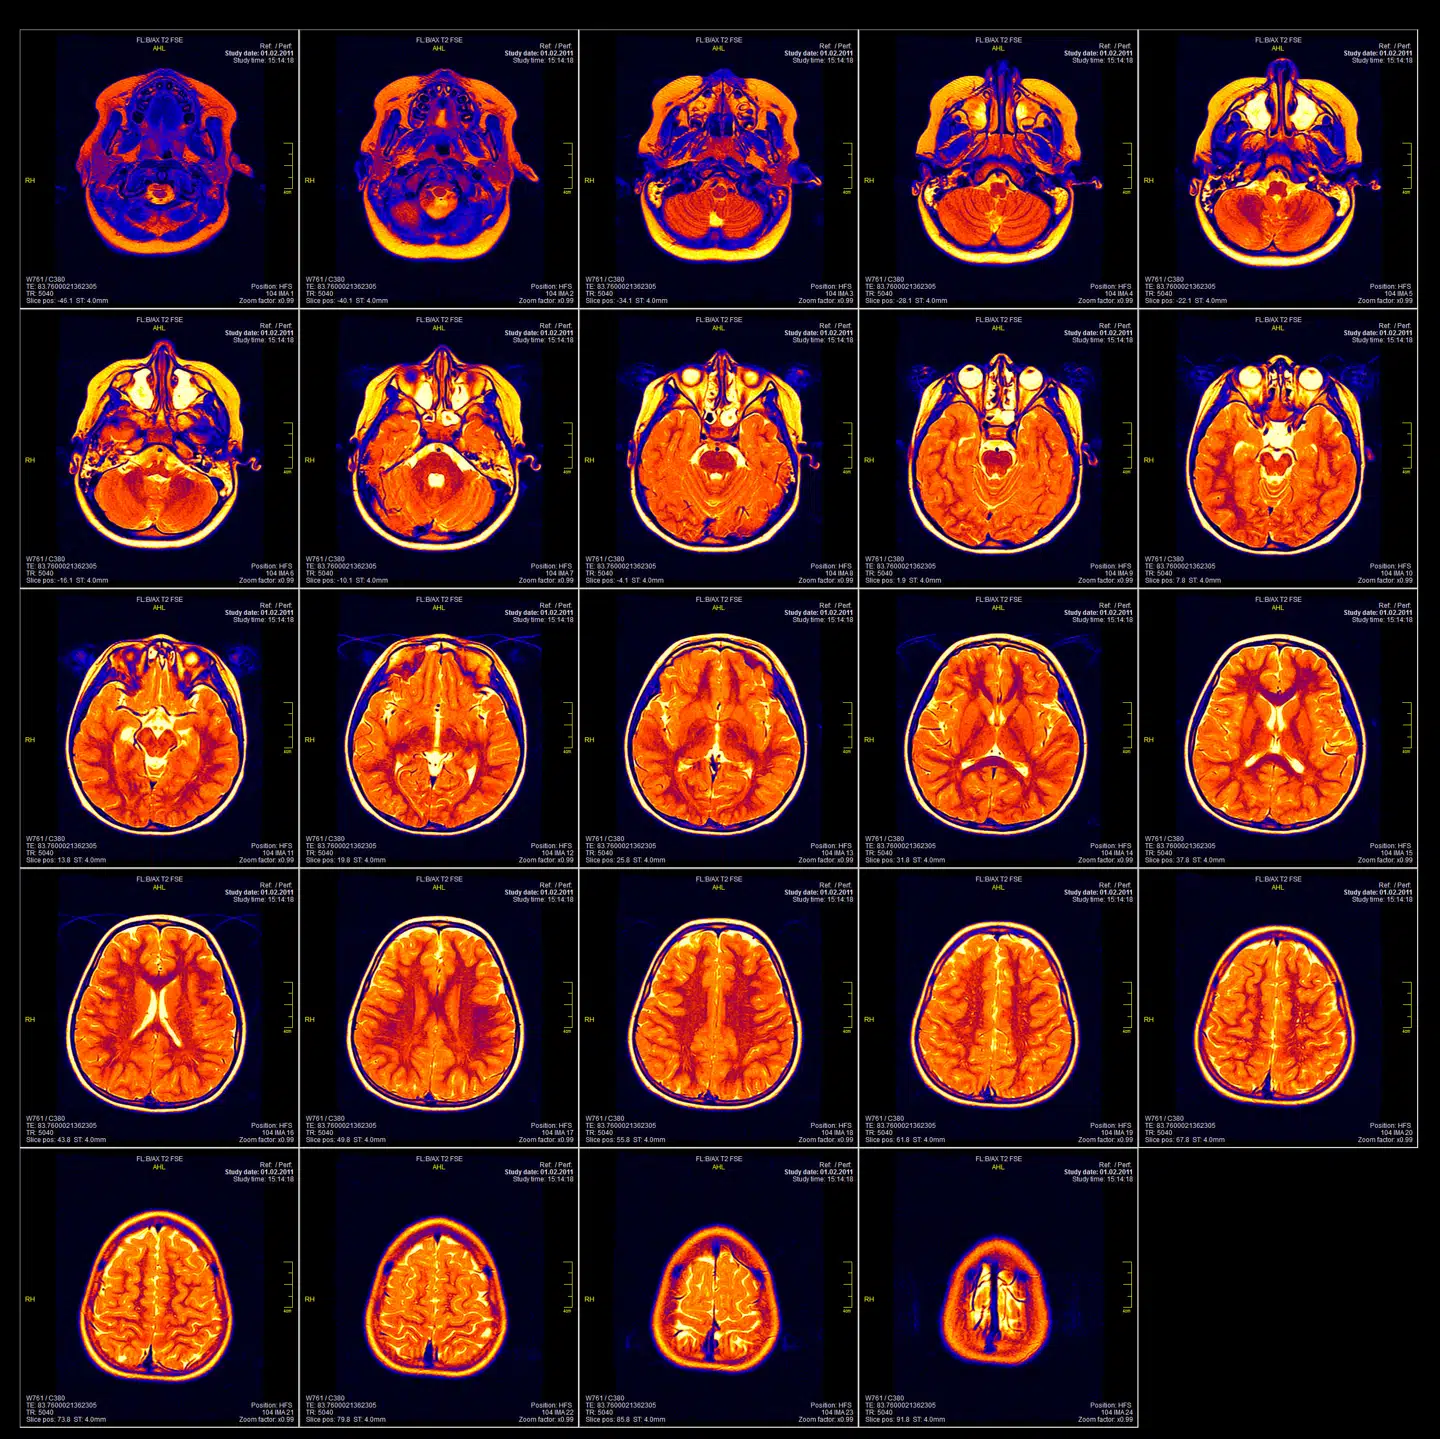

Neuroetik. Techgiganter vil gøre hjerneteknologi til hvermandseje, og det har fået forskere til at advare om tankeovervågning. Men er det overhovedet muligt?